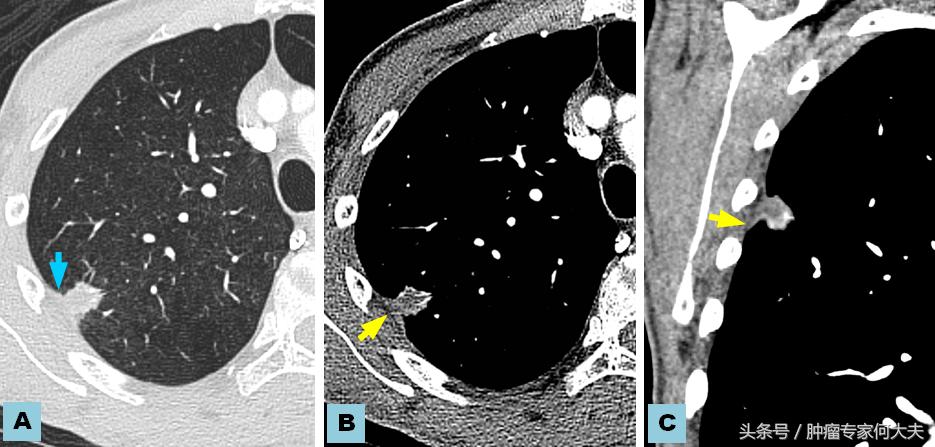

肺影像学

在第二年接近第三年的那次复查中,小豆被医生告知右肺也长了瘤子,医生建议小豆穿刺活检,小豆还是比较配合的,做了肺穿刺活检术,术后病理结果证实也是肺腺癌,和以前病理结果一样,医生推测可能是转移,并对取下的组织进行了基因检测,仍然没有检测到敏感突变基因,但医生建议小豆可以尝试口服“易瑞沙”,因为在生病的2年多时间里,小豆研读了很多肺癌的专业书籍,对肺癌的知识了解甚多,因此她同意了口服靶向药,在口服靶向药的两个月里,除过面部皮疹,没有其他不良反应,但用药三个月后,复查肺部CT,病灶依然没有明显变小迹象。医生考虑无效,于是就把靶向药停了。没有任何治疗,她还能撑多久?她自己不知道,医生们也众说纷纭,反正总体是时间不会太久,有的医生说也就半年一年左右,小豆说当时自己想“反正都这样了,与天争命也无济于事,静静等待未来会发生什么”。

就这样,读书、看报、上网,有时候和朋友出去游游逛逛,虽然癌症在身,她不能积极作为,只能听天由命,但是半年过去了,右肺出现的病灶生长势头不明显,一年过去了,两年过去了,三年过去了,一直在复查,但是复查的结果总是说变化不显著。但医生仔细对比三年之初与三年之末(最近)的片子,瘤子是有所长大,但都长的不算多,个别小病灶甚至自然变小。 最近,小豆说自己喘的明显了,夜里咳嗽厉害,难以成眠,要来查查,我给做了胸部CT检查,结果提示两肺多发占位病变,对比了她3年前刚发现右肺时的片子,这次明显变大,目前尚未做出诊疗计划。但对于小豆这样的病人,实属少见。人类对于肿瘤的认识仍然处于很原始的阶段。就拿肺癌来说,现代医学研究算是比较成功的一种瘤种,已经认识到一部分肺癌患者因为存在某些基因突变可以从治疗中获益,但是没有突变的患者并不是一定就很危险,个体差异相当大。希望每个人不要因为得了肿瘤,就自暴自弃。